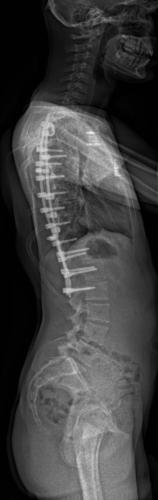

Images de scolioses opérées 16 janvier 202418 janvier 2023 par Damien Scoliose Thoracique 3 Scoliose thoracique D - Cliché pré-opératoire de Face Scoliose thoracique D - Cliché pré-opératoire de Profil Scoliose thoracique D - Cliché post-opératoire de Face Scoliose thoracique D - Cliché post-opératoire de Profil Aspect de la cicatrice à distance de l'intervention